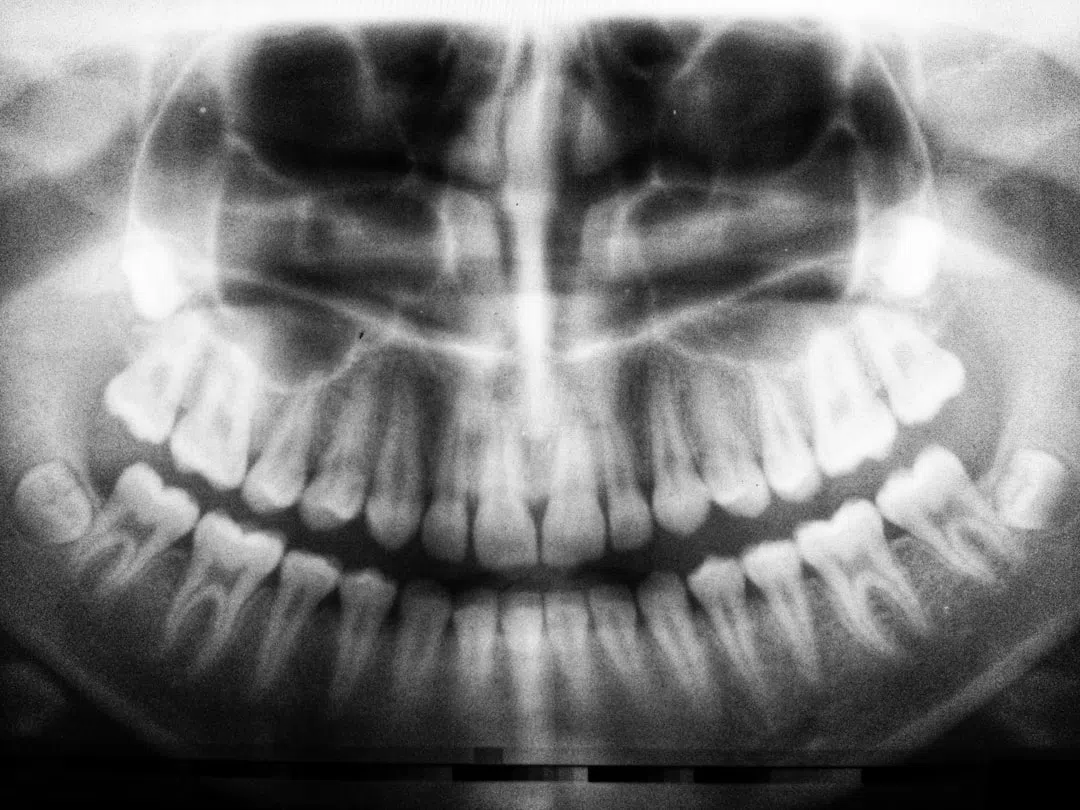

저는 지난 몇 년 전, 치아 임플란트 수술을 받으면서 신체적, 정서적으로 겪은 경험들을 바탕으로 임플란트 후 관리법에 대해 깊이 연구하게 되었습니다. 처음 수술실 문을 나서던 그 순간부터 회복 과정에 이르기까지, 저는 붓기, 통증, 회복 기간 등 여러 문제에 직면했습니다. 이 글에서는 제가 직접 겪은 임플란트 수술 후 붓기 줄이기, 회복 기간의 실제 경험, 그리고 통증 완화를 위한 다양한 방법들을 상세히 소개하고자 합니다.